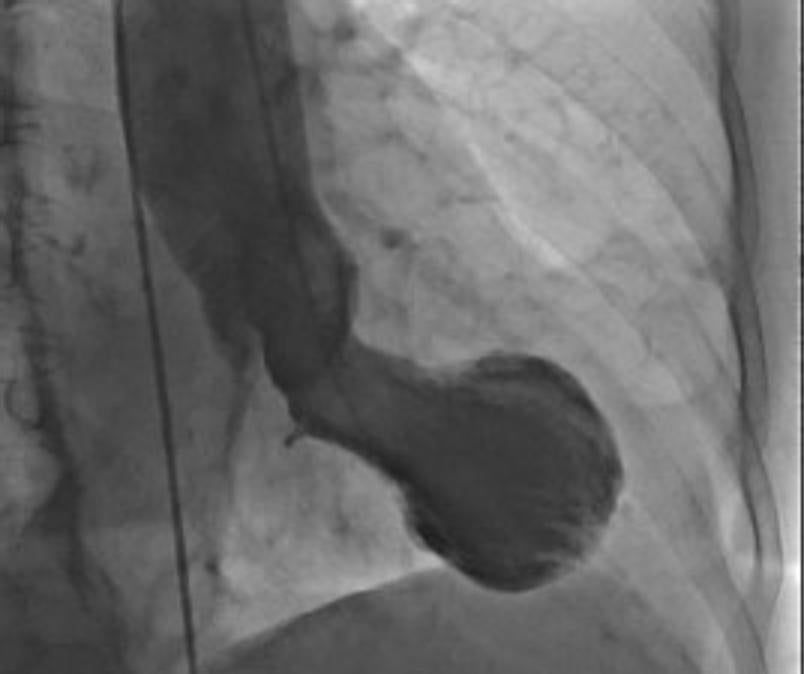

Este es un corazón de Takotsubo, que muestra la forma típica que se asemeja a una trampa de pulpo japonesa. Professor Christian Templin, University Hospital Zurich

Este síndrome se caracteriza por un repentino debilitamiento temporal de los músculos del corazón que hace que el ventrículo izquierdo del corazón se hinche en la parte inferior mientras el cuello permanece estrecho, creando una forma que se asemeja a una trampa japonesa para pulpos, de la que obtiene su nombre (Takotsubo).